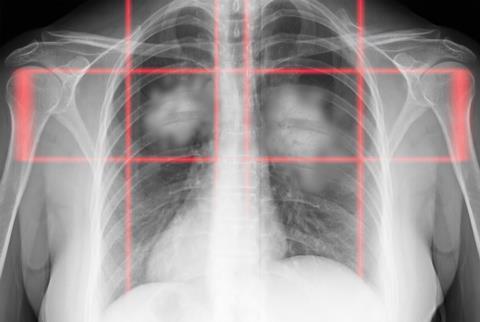

A new comprehensive review reveals how lactylation – a post-translational modification driven by lactate – functions as a critical metabolic regulator in lung cancer progression and treatment resistance.

A newly published review has outlined an emerging biological process that may play a crucial role in the progression of lung cancer and its resistance to treatment.

Led by Yong Xu and colleagues at Shanghai Pulmonary Hospital, the study examines lactylation, a post-translational modification driven by lactate. The findings suggest that lactate, once dismissed as a mere metabolic waste product is actually central to a complex signalling network linking cellular metabolism to epigenetic regulation.